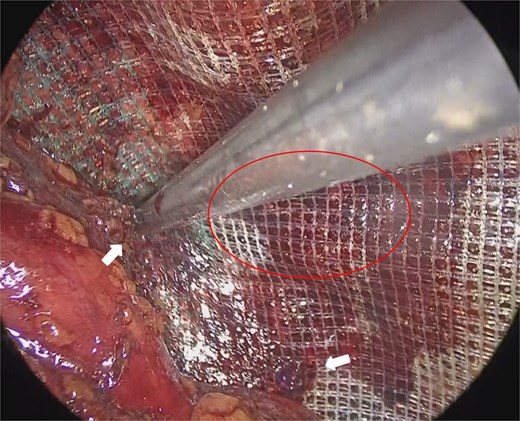

On the left, the recurrent hernia orifice was identified adjacent to one of the mesh plugs, with the pseudosac firmly adherent to the plug (Fig. 5). After careful sharp and blunt dissection, a recurrent orifice was clearly exposed in the left pubic region and classified as R1M2 (Fig. 6). A circumferential margin of ~2.5 cm was secured around the defect. The laterally placed plug did not interfere with the repair and was left in situ. A 15 × 10 cm self-gripping mesh (ProGrip™) was placed to cover the recurrent defect with a 2.5 cm margin and was supplemented with tacker fixation because overlap was limited (Fig. 7). Although the left-sided mesh covered the right hernia orifice, overlap on the right was insufficient (Fig. 8), so an additional mesh was applied for reinforcement. The right-sided high peritoneal incision was sutured and closed in a standard fashion (Fig. 9). The postoperative course was uneventful. At 5-month follow-up, there was no clinical evidence of recurrence.

Mesh fixation using a tacker (arrows). The distance from the recurrent hernia orifice (circle) was limited.

Mesh placed on the left side (circle) and secured with tackers. The right-sided hernia orifice (circle) was fully covered.

A key factor in achieving durable hernia repair is securing adequate mesh overlap. The European Hernia Society recommends at least 3–4 cm in all directions and 4–5 cm for large or recurrent hernias [9]. Although the 2024 Japanese guidelines do not specify an exact value, expert consensus similarly supports ≥3 cm for primary and 4–5 cm for recurrent cases, generally using meshes of at least 10 × 15 cm [4]. In our case, overlap was limited to ≈2.5 cm because of a residual plug and scarring. To compensate, a self-gripping mesh and selective absorbable tacker fixation were used within safe zones (Cooper’s ligament, medial edge of the internal ring) to avoid neurovascular injury. Nevertheless, limited overlap remains a potential cause of re-recurrence. Thorough preoperative planning and intraoperative flexibility—including mesh augmentation or modification of the approach—are essential for secure and lasting repair.